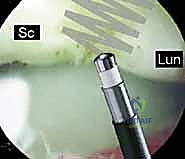

* Scapholunate Interval: This is where we focus for SLIL pathology. The SLIL is best visualized through the 3-4 portal, with probe insertion through the 4-5 or 6R portal. We'll follow the radioscapholunate ligament (ligament of Testut) proximally to locate the SLIL.

* Geissler Grades: We're looking for the Geissler classification:

* Grade I: Attenuation of the SLIL, but stable to probing. No gapping.

* Grade II: Partial tear with an unstable tissue flap, but no frank gapping.

* Grade III: Complete tear with dynamic gapping, but no static instability.

* Grade IV: Complete tear with static gapping and carpal malalignment (DISI).

* Occasionally, an avulsed portion of the SLIL may make visualization through the 3-4 portal difficult. In this situation, we can transfer the arthroscope to the 6R portal and direct it radially for a better view.